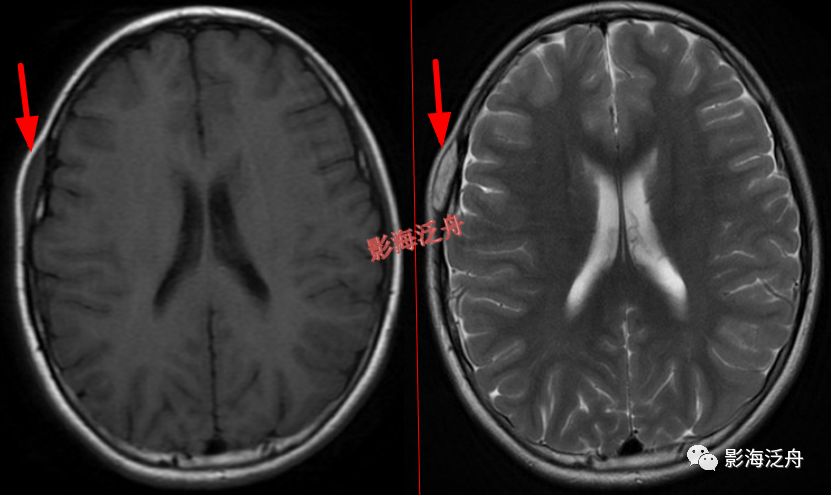

头皮下血管瘤以及皮脂腺瘤是非常常见的,单也很容易漏诊,尽管临床意义不大,但还是应当避免漏诊,毕竟现在的大家的处境一言难尽~

右侧额部头皮下血管瘤。患者为11岁女性,是本病的高发年龄段,这个结节要是漏诊,恐怕会有麻烦。